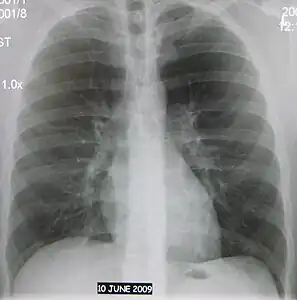

Normal AP CXR

AP CXR showing left lower lobe pneumonia associated with a small left sided pleural effusion -

AP CXR showing right lower lobe pneumonia -

AP CXR showing pneumonia of the lingula of the left lung -

Right upper lobe pneumonia as marked by the circle. -

Left upper lobe pneumonia with a small pleural effusion.